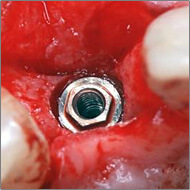

1983年に東京歯科大学が日本で最初にオッセオインテグレーテッドインプラントの概念とその治療法を紹介して以来、口腔インプラント療法は急速な進歩を遂げ、現在では、咀嚼障害や審美障害の改善手段として、長期間にわたる良好な治療成績が確認されています。千葉歯科医療センター口腔インプラント科では、近年、ますます複雑、多様化する患者様のニーズに応えるため、最新の設備や充実したスタッフを配備し、安心・快適・便利を実感できる診療科をめざしています。また、インプラント埋入手術時の鎮静法の併用、基礎疾患を持っている患者様の全身管理下での処置、骨移植、口腔内軟組織移植等の関連手術を行う設備体制を整え、大学医療機関の特色と利点を最大限に生かした治療を心がけています。

1~2本と歯の欠損が少ない場合でのインプラント治療は、従来の治療法(ブリッジや入れ歯)と比較して両隣の歯を削ったりする必要がなく、残っている歯に負担をかけないですみます。また、前歯の治療においては隣在歯と調和のとれた高い審美回復が必要とされることから、骨と粘膜の高度なマネージメントが必要とされます。口腔インプラント科では、高いレベルの審美修復治療の結果を達成するよう専門スタッフが対応しています。

部分入れ歯や総入れ歯などを使う必要がある歯の欠損に対するインプラント治療では、入れ歯と比較して違和感が少なく、咀嚼や発音などの機能回復が期待できます。また、欠如部以外の残存歯の治療が必要になる場合も、初診時からメンテナンスに至るまで一貫した包括的治療を行っています。また、インプラント埋入部位の骨が不足していたり、その他の要因でインプラント療法を断念されていた患者様に対しても、各分野の専門スタッフが高度な診断技術により対応をしています。